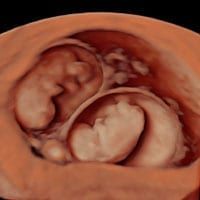

10 Week Scan

This is the earliest and most technologically advanced anomaly scan at 10 weeks which aims to exclude 10 severe fetal anomalies visible at this stage. 10 weeks of pregnancy is the best time to use safe 3D medical technology for your baby’s health checkup.

Undoubtedly this scan is the best ultrasound examination to have together with NIPT.